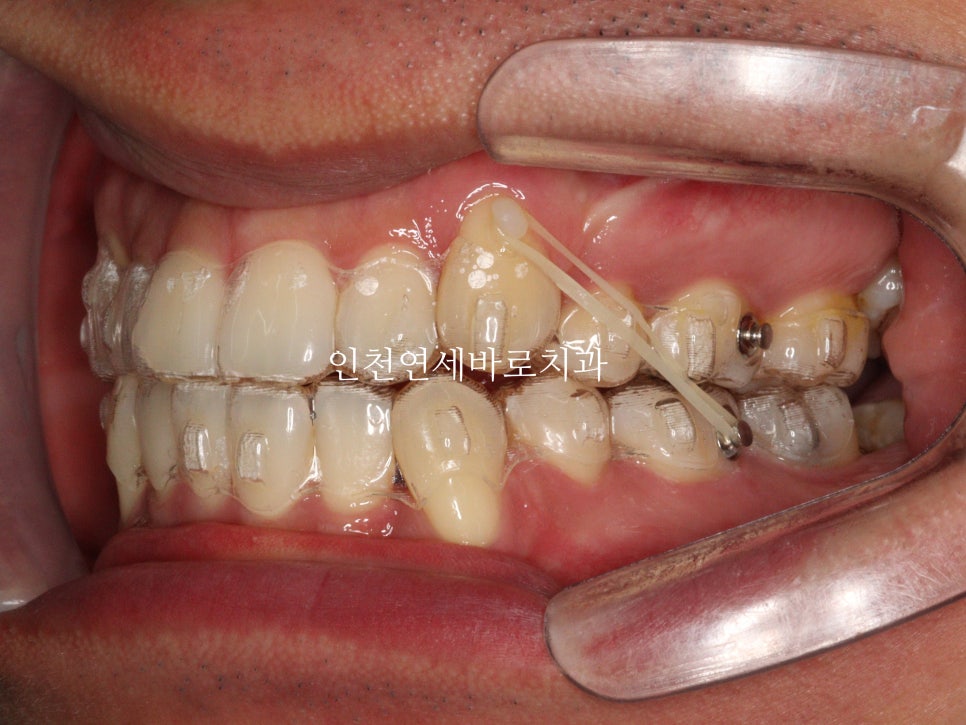

발치 교정으로 인비절라인 끝난 환자분으로

왼쪽은 덧니의 발치교정으로

하이캐나인 이라고 불리는

위쪽 높이 위치해있는 송곳니의 교정치료의 경우, 많은 경우에 고무줄이 추가로 필요합니다.

인비절라인 자체도 열심히 껴야하지만,

이 환자분의 경우에는 12시간 정도 고무줄도 함께 착용했습니다.